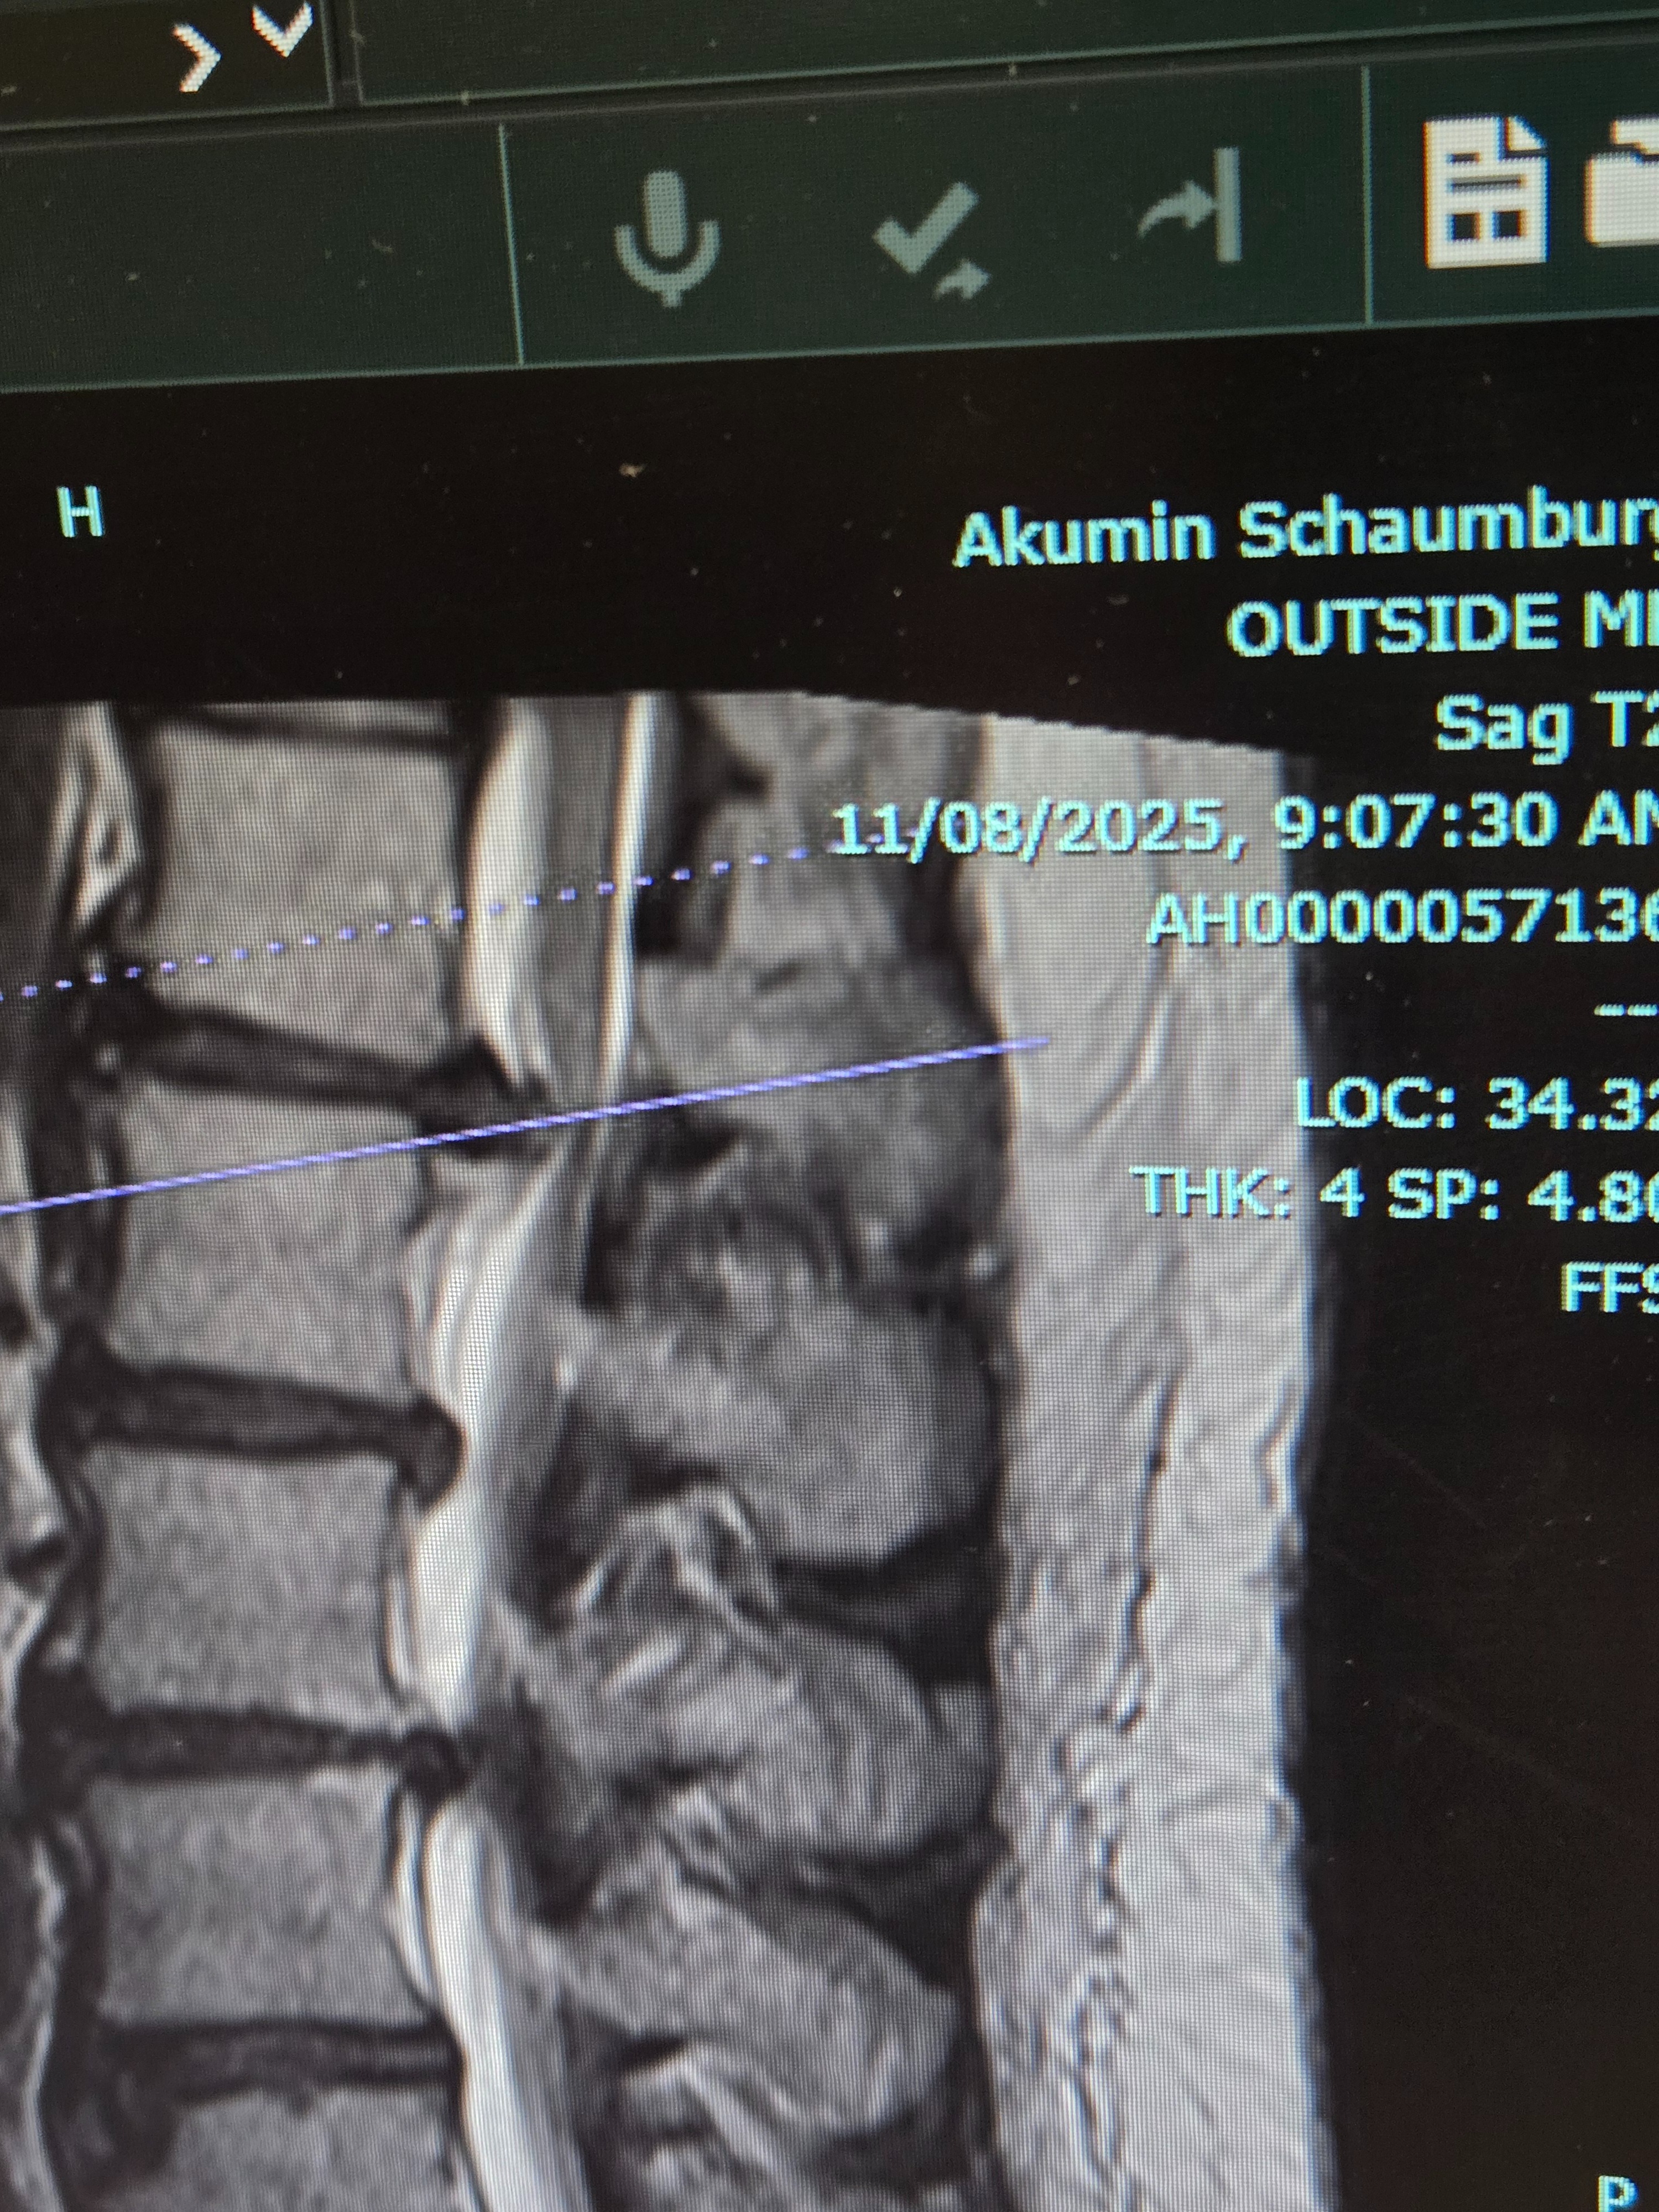

I recently had spinal surgery to deal with severe nerve pain that had been affecting my day-to-day life. During the surgery, there were unexpected complications- spinal tear and fluid leakage- that kept me in the hospital longer than planned and left me facing a much longer recovery and medical costs than I was prepared for.